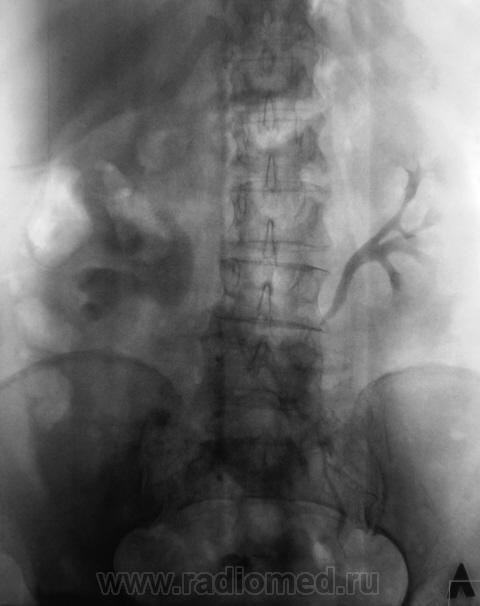

Пациент направлен на внутривенную урографию. Диагноз - "Мочекаменная болезнь?". Врач УЗИ сообщил, что "камни" с обеих сторон. По поводу картины сильно не распространялся.

1. Пациент? Или пациентка? (судя по ширине малого таза и наличия в нем обызествления характерного в большей степени для обызествленного фиброматозного узла);

2.Крупный коралл правой почки и камень лоханки левой почки;

3.Блок правой почки, как следствие МКБ (камни в средней трети правого мочеточника);

4. Отток слева не нарушен;

5.Округлый дефект выполнения в области устья правого мочеточника вполне может быть обьяснен наличием уретероцеле, а тогда станет понятна и причина камнеобразования справа.

Пациентка, наша коллега, врач.

Фрагмент с мочевым пузырем.